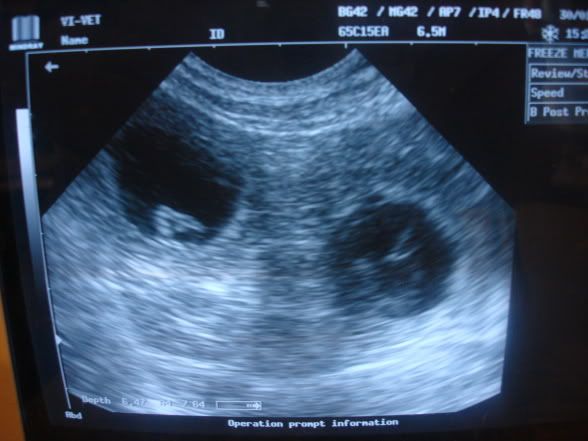

Asiaczek Posted February 3, 2010 Posted February 3, 2010 [quote name='Aussie']Namówiona przez Magdę Mudikową, zgłaszam się i ja :-) W sobotę moja Astuszka miała usg i i okazało się, że w jej brzuszku rosną małe aussikowe fasolki. Napewno jest ich kilka. A to dwie z nich: Stresuję się, bo to pierwsza ciąża w mojej karierze hodowcy, w dodatku bardzo wyczekana. Pierwsze krycie nie wyszło, więc zdecydowałam się na sprowadzenie mrożonki. Inseminacja byłą metodą norweską, więc tym bardziej bardzo się cieszymy z panem doktorem Marczakiem, że ciąża jest mnoga. Aussie - cieszymy się razem z Tobą i trzymamy kciukasy! [quote name='Judit']niestety ale nie dałam rady przekonać rodziców... serduszkowa panna idzie do naszych znajomych z Lublina którzy już jednego psiaczka od nas mieli. Także będzie mieszkać niedaleko nas i zobaczymy co z niej wyrośnie. No i co wyrośnie z reszty szczenioli. ;) Było to bardzo fajne skojarzenie i jeśli dzieci okażą się fajne to możliwe że powtórzymy krycie i wtedy może coś zostawimy. Czas pokaże :p jednak ja dalej nie wyobrażam sobie dnia w którym pojedzie do nowego domu... :placz: mimo że wiem że będzie jej tam bardzo dobrze. A, czyli będzie "na widoku". To dobrze.:) Pzdr. Quote